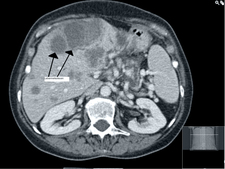

CT is a procedure of X-ray diagnostics creating cross-sectional pictures of the body. During CT an X-ray machine, consisting of an X-ray tube assembly and a radiation detector on the opposite site, continuously rotates around the body, following a circular or spiral path to obtain a multiplicity of radiographs from different directions (projections). A computer program is used to transform these projection images into cross-sectional non-overlapping pictures of high-contrast displaying tissues of different density in well distinguishable shades of grey.

The radiation dose to the patient caused by CT is relatively high as compared to radiography.